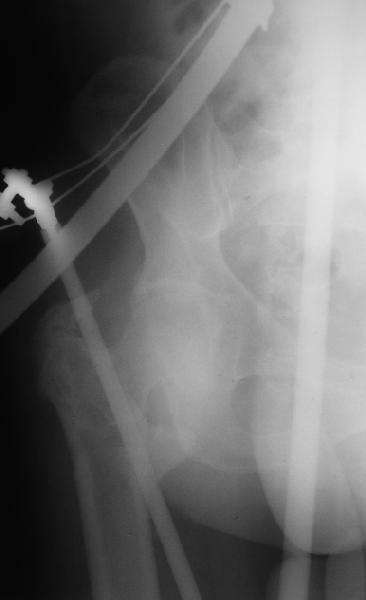

На прошлой неделе оперировали похожего пациента. 2 года после неудачного остеосинтеза PFN в другом регионе. После удаления остатков железа выявилось несращение вертельной области.

В такой ситуации важно устранить варусную деформацию. При использовании гвоздя это непросто. Поэтому в число рассматриваемых

вариантов стоило бы включить вальгизирующую остеотомию с фиксацией 130-градусной клинковой пластиной или DHS.

Если есть сильное желание фиксировать все-таки гвоздем, советовал бы ввести мощный "джойстик" параллельно оси шейки бедра близко к ее задней стенке, сделать поперечную межвертельную остеотомию и использовать дистрактор таз-бедро.

Поскольку в нашем случае выявилась подвижность, мы наложили дистрактор таз-бедро на 3 дня, и сделали остеосинтез гаммой без остеотомии. То, что произошла "корригирующая остеоклазия" в подвертельной области, выявили после введения гвоздя. Пациент уже уехал домой, будем наблюдать.